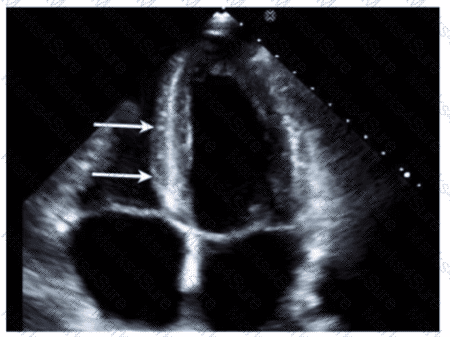

A patient presents with tender, red lesions on their fingers and toes (Osier nodes). Which finding is most likely?